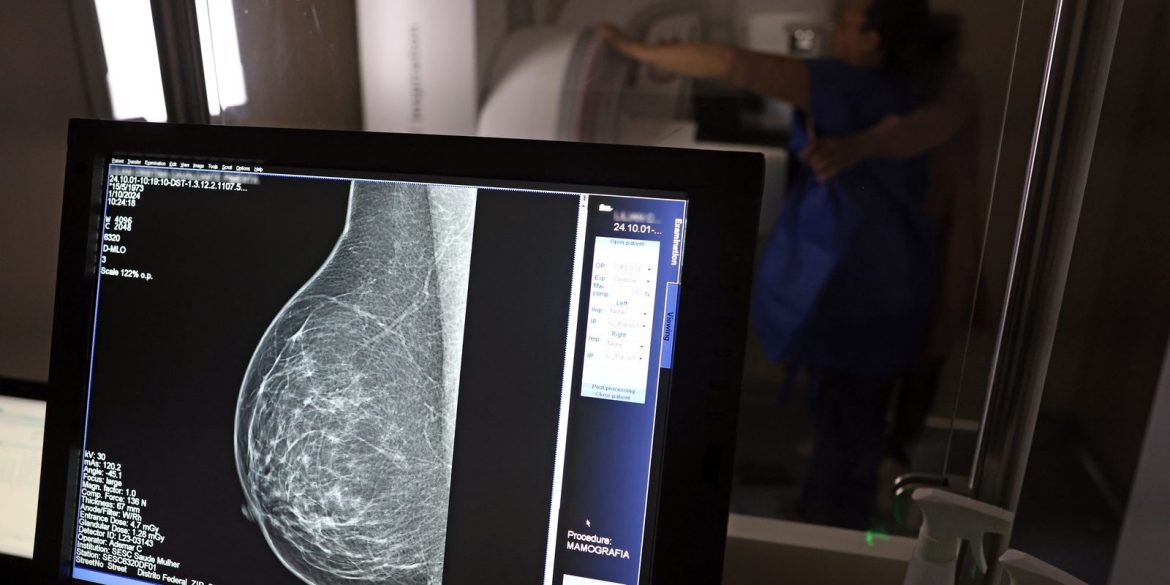

Casa SaúdeFalta de acesso a mamógrafos limita prevenção do câncer de mama

Falta de acesso a mamógrafos limita prevenção do câncer de mama

No mês de conscientização sobre o câncer de mama, um relatório destaca a importância de acesso igualitário ao rastreamento e tratamento da doença. Segundo o Atlas da Radiologia no Brasil, do Colégio Brasileiro de Radiologia e Diagnóstico por Imagem (CBR), o acesso aos mamógrafos ainda é um desafio.

O país tem 6.826 equipamentos registrados, sendo 96% em funcionamento. Metade deles está disponível no Sistema Único de Saúde (SUS), responsável por atender 75% da população. Isso equivale a 2,13 mamógrafos por 100 mil habitantes dependentes do SUS.

Na saúde suplementar, que cobre 25% da população, o cenário é mais favorável: 6,54 aparelhos por 100 mil beneficiárias, quase o triplo da rede pública. O Acre exemplifica essa disparidade — são 35,38 mamógrafos por 100 mil habitantes na rede privada, contra 0,84 no SUS.

Há disparidades regionais. Roraima tem a menor proporção (1,53 por 100 mil), seguida do Ceará (2,23) e Pará (2,25). A Paraíba lidera o ranking (4,32), à frente do Distrito Federal (4,26) e do Rio de Janeiro (3,93).

O Brasil tem uma cobertura muito baixa de mamografias: 24%. O ideal recomendado pela Organização Mundial da Saúde é de 70%. Mesmo em lugares como o estado de São Paulo, que tem a maior concentração de mamógrafos do país, a taxa gira em torno de 26%.

Em setembro, o Ministério da Saúde ampliou as diretrizes de rastreamento, recomendando que mulheres entre 40 e 49 anos realizem mamografias, mesmo sem sintomas. De acordo com o Instituto Nacional do Câncer (Imca), mais de 73 mil mulheres recebem o diagnóstico de câncer de mama anualmente no Brasil.